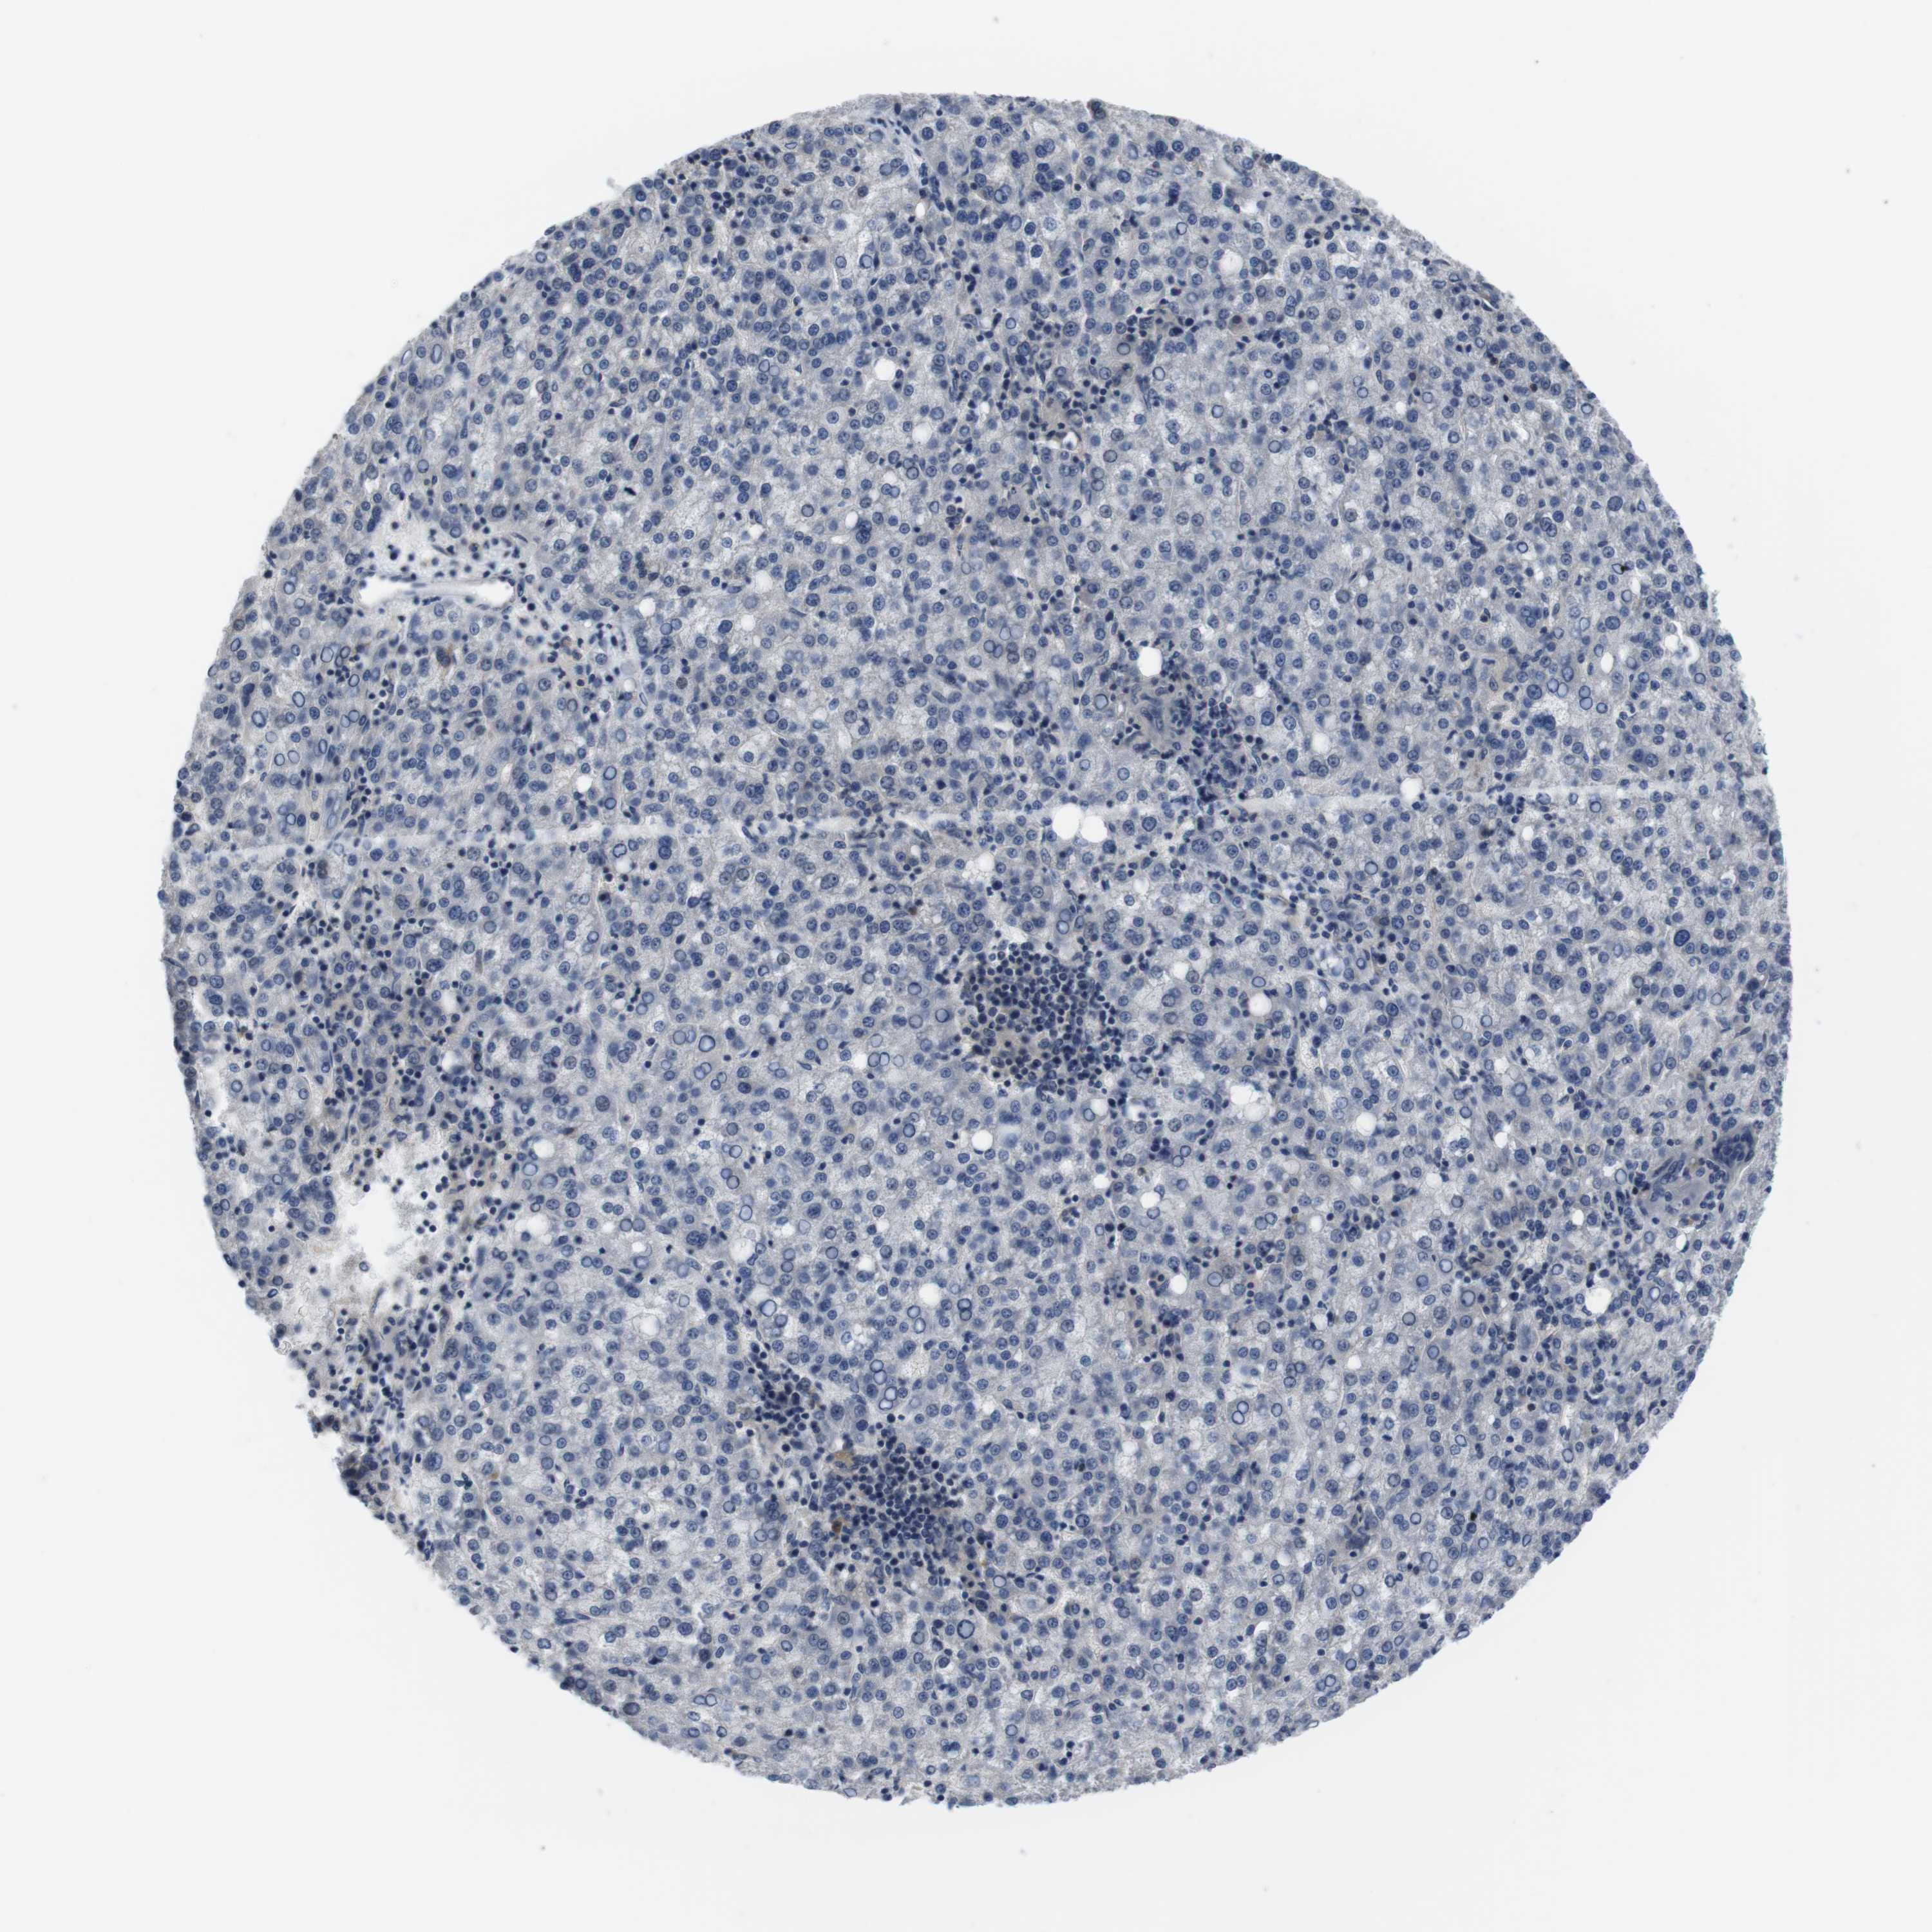

LIVER CANCER - Protein expressioni

A mouse-over function shows sample information and annotation data. Click on an image to view it in a full screen mode. Samples can be filtered based on level of antibody staining by selecting one or several of the following categories: high, medium, low and not detected. The assay and annotation is described here.

Antibody stainingi

Antibody staining in the annotated cell types in the current human tissue is reported as not detected, low, medium, or high, based on conventional immunohistochemistry profiling in selected tissues. This score is based on the combination of the staining intensity and fraction of stained cells.

Each image is clickable and will lead to virtual microscopy that enables deeper exploration of all samples and also displays staining intensity scores, fraction scores and subcellular localization as well as patient and tissue information for each sample.

Antibody HPA001464

Antibody CAB010209

Staining

High

Medium

Low

Not detected

Intensity

Strong

Moderate

Weak

Negative

Quantity

>75%

75%-25%

<25%

None

Location

Nuclear

Cytoplasmic/membranous

Cytoplasmic/membranous,nuclear

Cholangiocarcinoma

Carcinoma, Hepatocellular, NOS